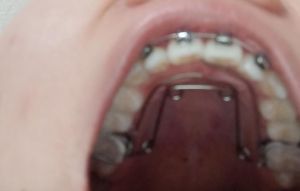

Nong hàm khi đeo niềng răng đau lâu không?

Em vừa đeo mắc cài vừa đeo nong hàm, 2 tuần nữa em đi Thái chơi mà không biết bao giờ thì quen có thể ăn nhai nuốt được nữa. Chứ giờ nuốt cháo em cũng thấy khó khăn lắm. Liệu cơn đau khi nong hàm kiểu này có kéo dài lâu không bác sĩ?

Em nong hàm hôm nay là ngày thứ 5, cảm thấy stress quá hic. Cả 5 ngày này, đừng nói tới ăn, uống nước còn khó, thậm chí em còn hạn chế nói, có khi gặp người lạ còn giả vờ không nói được, bởi vì nong hàm xong thì bị nói ngọng, thấy rất mất tự tin nên không muốn nói. 1 phần khác là vì lúc phát âm lưỡi bị đau rát. Tới hôm nay lưỡi tớ rát như kiểu sắp rách ra tới nơi ấy, rất là xót luôn. Nên em không biết tình trạng này có phải là bình thường với những người nong hàm không, chứ đau lưỡi với mất tự tin muốn từ bỏ